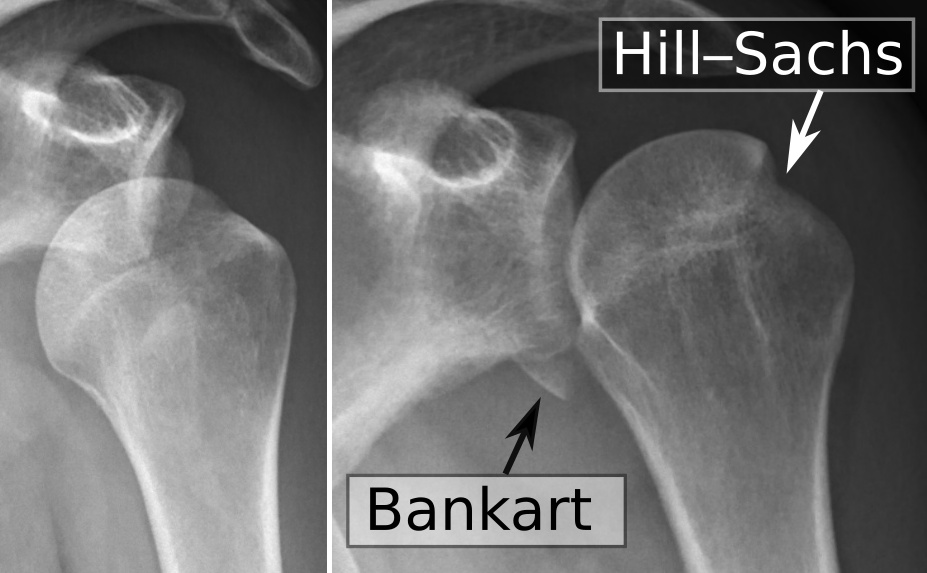

In einigen Fällen können bei einer traumatischen Schulterluxation mehrere Strukturen beschädigt werden. Zunächst kann einmal das Bindegewebe der Kapsel und/oder des Labrums gedehnt werden oder reißen. Zum anderen kann sich eine knöcherne „Bankart-Läsion“ entwickeln, bei der es durch den Aufprall zu einer Fraktur am unteren Ende der Schulterpfanne kommt. Dies geht häufig mit einer „Hill-Sachs-Läsion“ einher, einer Delle in der Schulterkopf selbst. Eine Röntgenaufnahme der Schulter kann dies entweder zeigen oder ausschließen.

Bei einer (traumatischen) Auskuglung ist es wichtig, dass eine Bildgebende Untersuchung durchgeführt wird, um weitere Läsionen und mögliche Brüche auszuschließen.